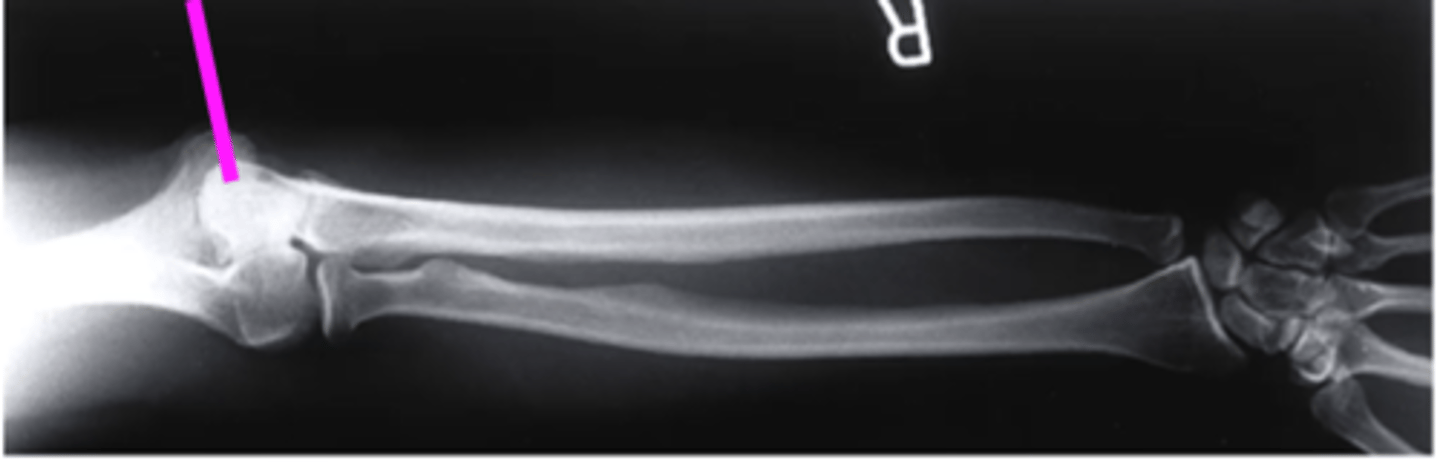

external oblique elbow

what view is this

radial head

what does the green line point to?

AP forearm

what view is this?

olecranon process

what does this pink line point to?

trochlea

capitulum

humeroradial joint

proximal radioulnar joint

radial tuberosity

radial styloid

distal radioulnar joint

scaphoid

lunate